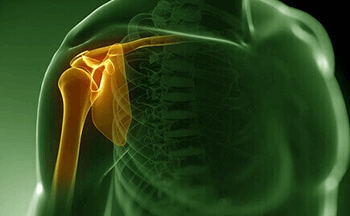

Shoulder joint complex is a combination of several joints that combine with tendons and muscles to allow a wide range of motion in the arm — from scratching your back to throwing a jawline. Any problem in the shoulder joint complex can be disturbing. The pain may be temporary or continuous and require medical diagnosis and treatment.

Most common shoulder problems fall into four major categories:

Tendon/bursal problems

Instability

Capsule problems

Bursa, afluid filled sac, which act as a cushion between the bones and the muscles. Excessive use of shoulder leads to inflammation of this sac.

Tendinitis- Tendon is a chord like structure that connects muscle to bone, inflammation of this chord can happen acutely after a strenuous workout or after acute calcium deposits or chronic tendinitis due to overuse, wear and tear, which can rupture after a small injury.

Shoulder Instability can occur when head of the arm bone comes out of the shoulder socket due to sudden injury. If the ligaments and capsule around the shoulder is loose or torn dislocation will happen frequently. Repeated episodes of such dislocations can be harmful to surrounding structures and may lead to arthritis, if not treated.

Arthritis also called wear and tear of the shoulder joint, can be due to several causes such as old age, untreated muscle tendon tears, instability, old sepsis or inflammation in the joint. A completely arthritic joint is most painful condition and will require a joint replacement surgery.

Stiff shoulder (Frozen shoulder/ Adhesive capsulitis)- Cause for stiff shoulder can be injury , surgery, any inflammation in and around the joint, arthritis, rarely any malignancy surrounding the shoulder joint. This issue is generally resolved with medications and rehabilitation but some may need a keyhole surgery to release the tight covering of the joint.